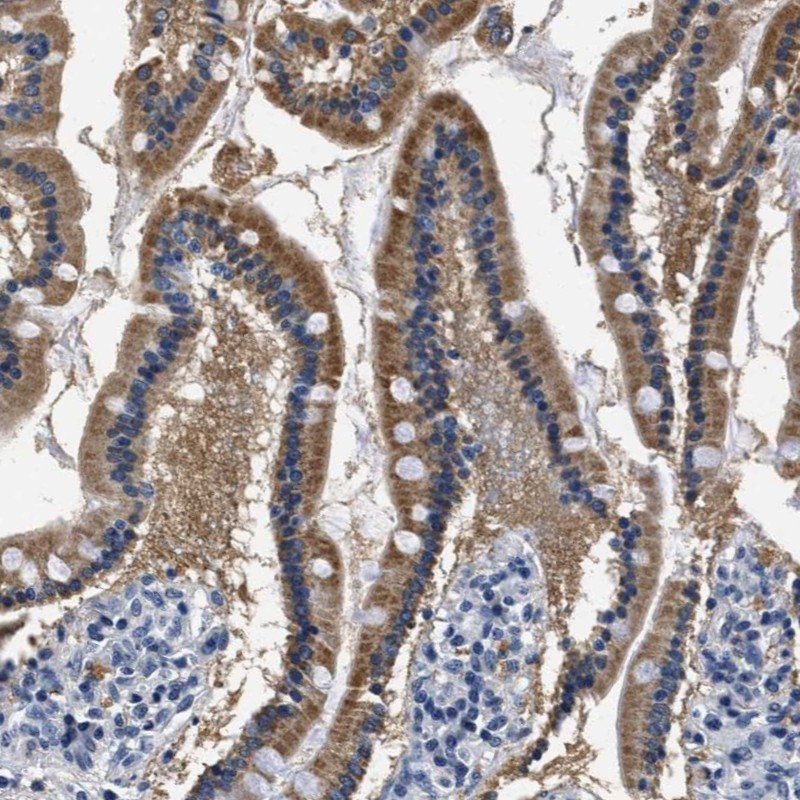

Immunohistochemical staining of human duodenum shows distinct positivity in glandular cells.